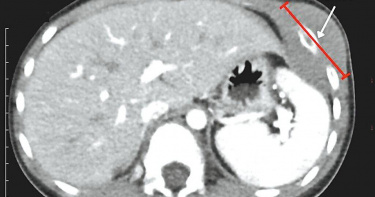

日前9歲男童發現左胸壁腫大隆起,雖不會疼痛,卻出現右大腿疼痛,疼痛慢慢轉移至右小腿,甚至無法行走,轉診至中山附醫,起初診斷右大腿骨遠端疑似骨髓炎,未料經大約5天治療效果不佳,檢查發現竟是B細胞淋巴芽型淋巴癌,所幸經化療後順利恢復。中山附醫兒童血液腫瘤科主任巫康熙指出,惡性淋巴癌是常見的兒童癌症,雖治癒率約有8成,但臨床表現十分多樣化,例如不明原因發燒、淋巴結腫大或下肢疼痛等皆十分常見。特別的是,淋巴癌不同於以往實塊腫瘤,它是由血液細胞癌變而來,透過藥物治療即能達到很好的療效。「孩子這麼小,打化療受得了嗎?」巫康熙表示,許多人都會如此心疼,其實,化療藥物一般是使用身高體重去計算劑量,同樣每公斤打1單位,兒童反而較無感覺,大人卻會受不了,因此兒童相對可以打較高的劑量,效果也比較好;男童經化療1個星期就復原近8成,化療1個月後腫瘤已完全消失,目前狀況穩定,於門診持續追蹤。兒童急診科主任謝宗明說,男童到院當天開始發燒至38.7度,左胸腫塊約5公分,而右膝活動已受限且有明顯壓痛,經檢查發現右大腿骨遠端疑似骨髓炎表現,住院接受抗生素治療約5天,改善進展緩慢,經會診血液腫瘤科醫師切片檢查,發現是B細胞淋巴芽型淋巴癌,全身已有多處轉移。醫師提醒,兒童下肢疼痛常會被認為是運動時扭傷、拉傷等,呼籲若不明原因下肢疼痛造成無法行走,排除外傷因素造成、初步治療成效未顯著,建議進一步檢查,早期發現較易治療。